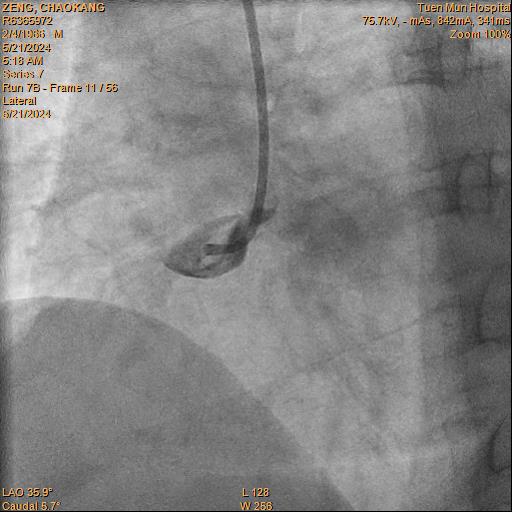

Coronary angiogram: LMS: normalLAD: diffuse disease up to 40% stenosis over p-mLADLCX: minor diseaseRCA: pRCA total occlusion with ? flapIRA = RCAPlan: PPCI to RCA

RCA is engaged with JR4.

Initially coronary dissection is suspected as pathology due to unusual angio appearance.

Difficult wiring is noted partly due to uncertain pathology. Eventually RCA is successful wired with Sion Black to distal. IVUS then confirmed giant pRCA coronary aneurysm with a large thrombus.

Size of aneurysm exceeded the US scan limits for measurement and angiographically > 10 mm. Multiple dilatation is attempted with 2.0 and 3.0 balloons, followed by clot aspiration with CAT Rx. . Despite of that, RCA remains in totally occluded with TIMI 0 flow.

Patient reported ongoing pain. Decided to proceed with stenting with the acknowledgement of likely malapposed proximal stent. Onyx Frontier 5.0/30 is deployed over proximal-mid RCA.. IVUS showed no stent edge dissection and malapposed proximal stent edge as expected.

The stent is dilated with 6.0 balloon. Integrellin infusion is given. TIMI III flow is restored.

Restudy coro is performed 3 months later. Very difficult RCA wiring is noted. RCA is wired with NS Runthrough, but failed to deliver IVUS. Second Runthrough wire crossed with crusade. IVUS showed stent landed on distal edge of aneurysm. Size of aneursym too big to be measured by IVUS and stented. Thrombus inside aneruysms is noted.

Reviewed is team discussion, it is decided for lifelong anticoagulation and not for further stenting proximally

This presentation shows a case of inferior STEMI with very big RCA aneurysm and thrombus formation inside.

Despite balloon dilatation and thrombectomy, flow is yet to be restored. Flow is restored after stenting. IVUS shows the aneurysm is so big beyond the limit of the machine, with thrombus inside. Stent landed on distal edge of aneurysm. Restudy coro showed TIMI III flow. Difficult rewiring requires use of crusade and 2nd wire. IVUS shows stent malapposed. No available coronary stent is big enough to cover the aneurysm. Reviewed in team meeting, it is decided for lifelong anticoagulation.

Despite balloon dilatation and thrombectomy, flow is yet to be restored. Flow is restored after stenting. IVUS shows the aneurysm is so big beyond the limit of the machine, with thrombus inside. Stent landed on distal edge of aneurysm. Restudy coro showed TIMI III flow. Difficult rewiring requires use of crusade and 2nd wire. IVUS shows stent malapposed. No available coronary stent is big enough to cover the aneurysm. Reviewed in team meeting, it is decided for lifelong anticoagulation.